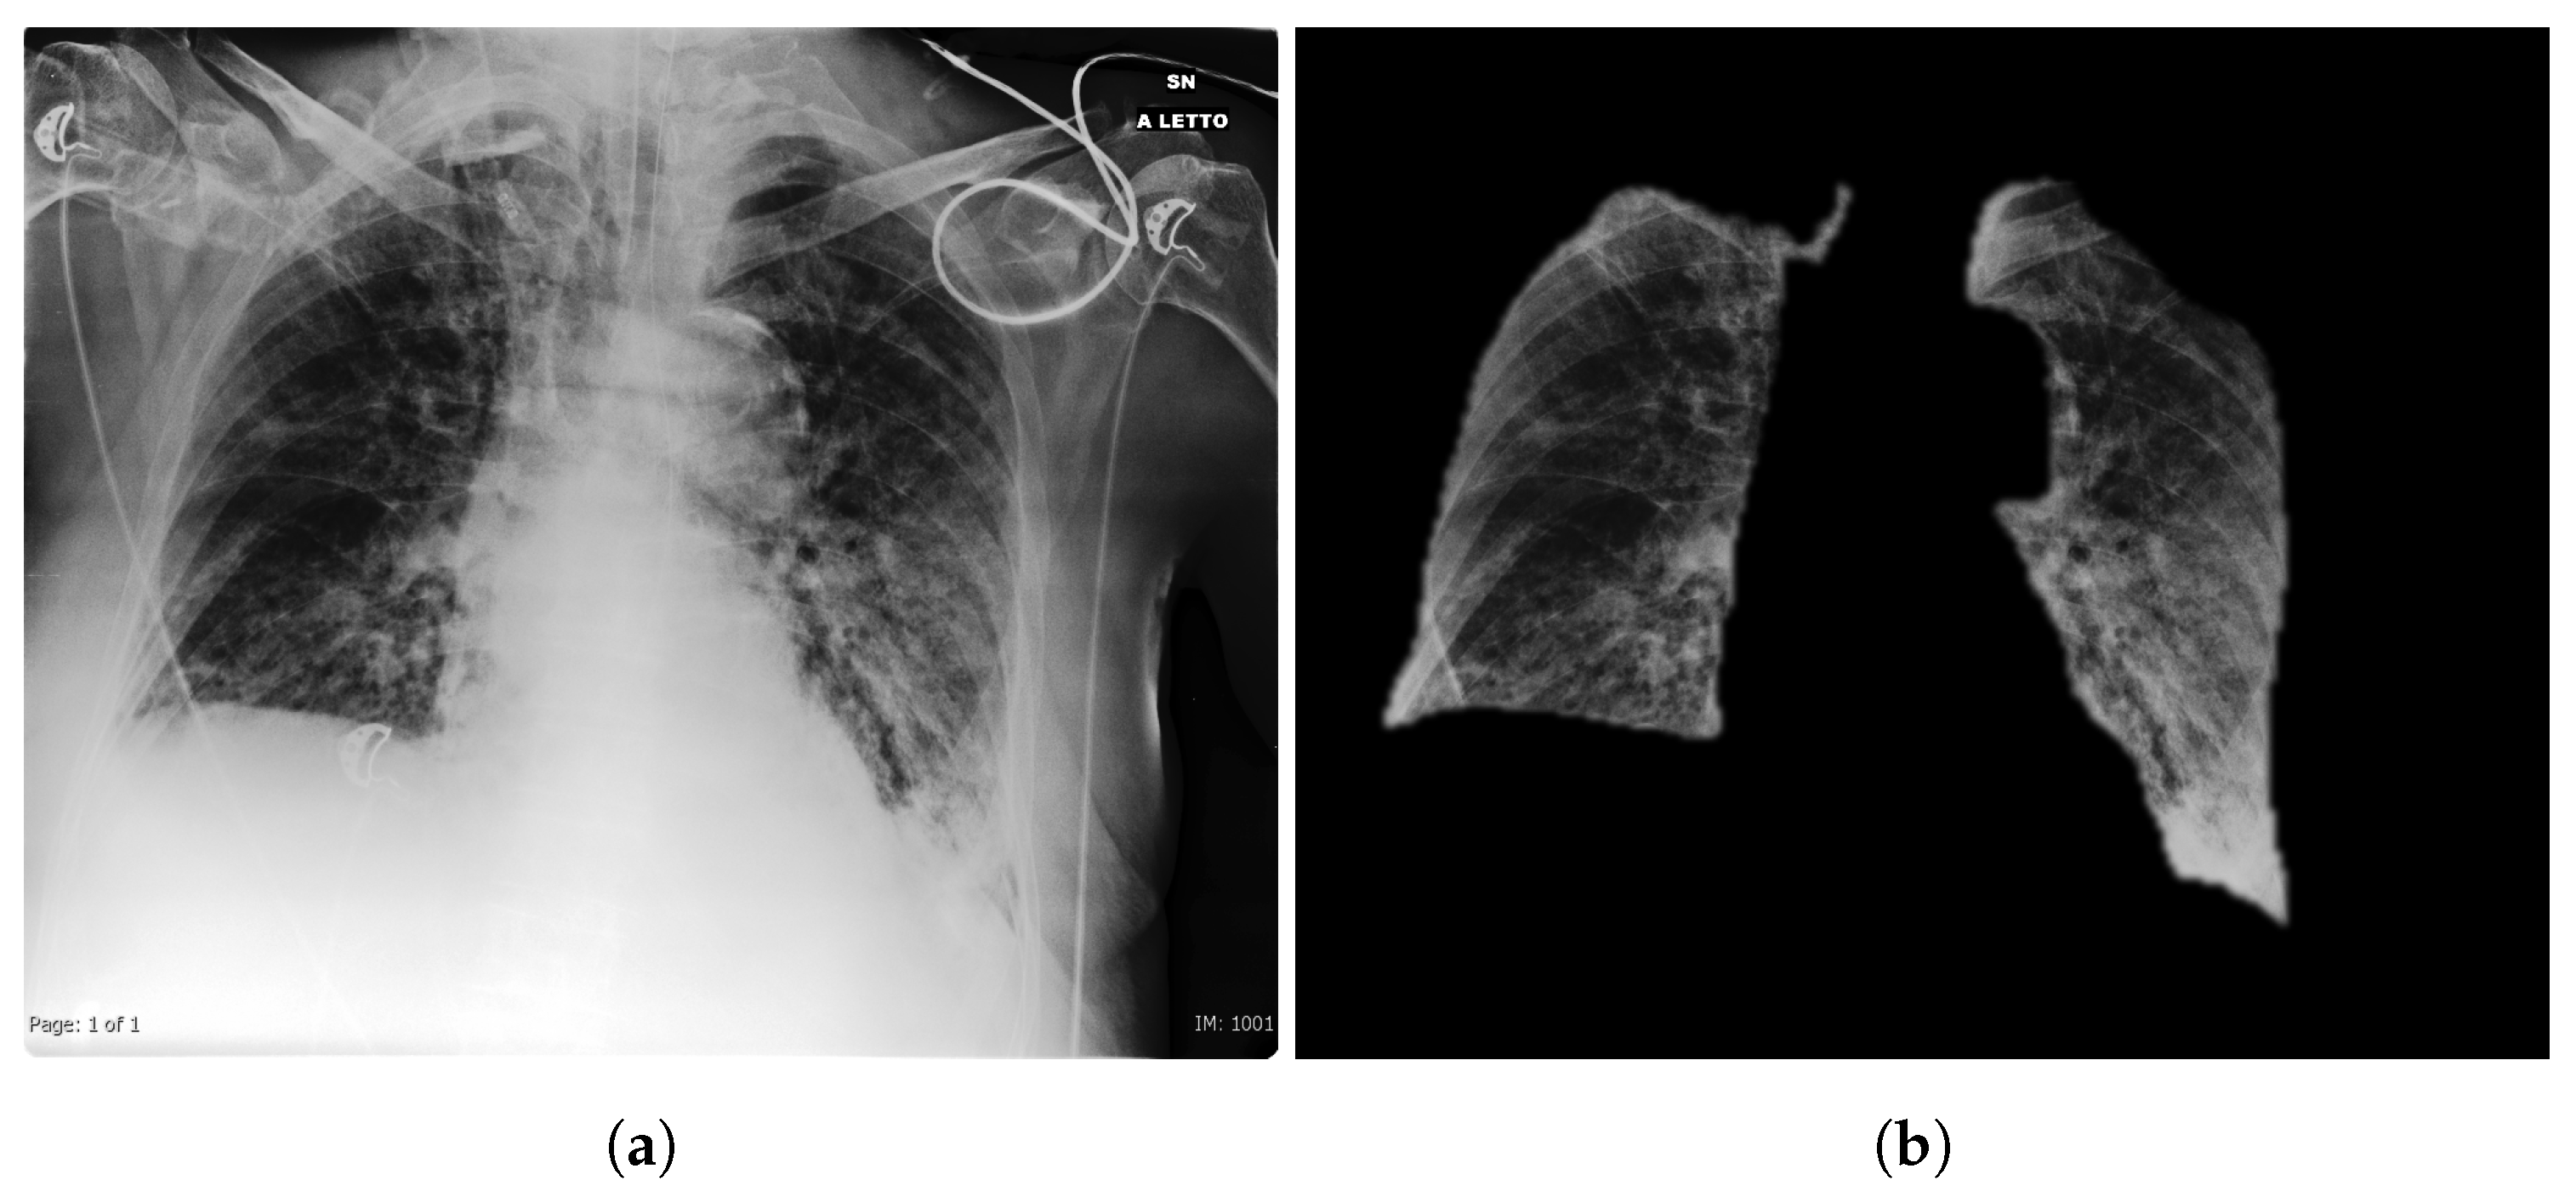

- Lung segmentation: the lung segmentation problem has been already faced and successfully tackled [26,27,28]. Being able to segment the lungs only, discarding all the rest of the CXRs, potentially prunes away possible bias sources, like for example the presence of medical devices (typically correlated to sick patients), various text which might be embed in the scan etc. In order to address this task, we train a U-Net [29] on Montgomery County X-ray Set and Shenzhen Hospital X-ray Set. The lung masks obtained are then blurred to avoid sharp edges using a 3 pixel radius. An example of the segmentation outcome is shown in Figure 2.